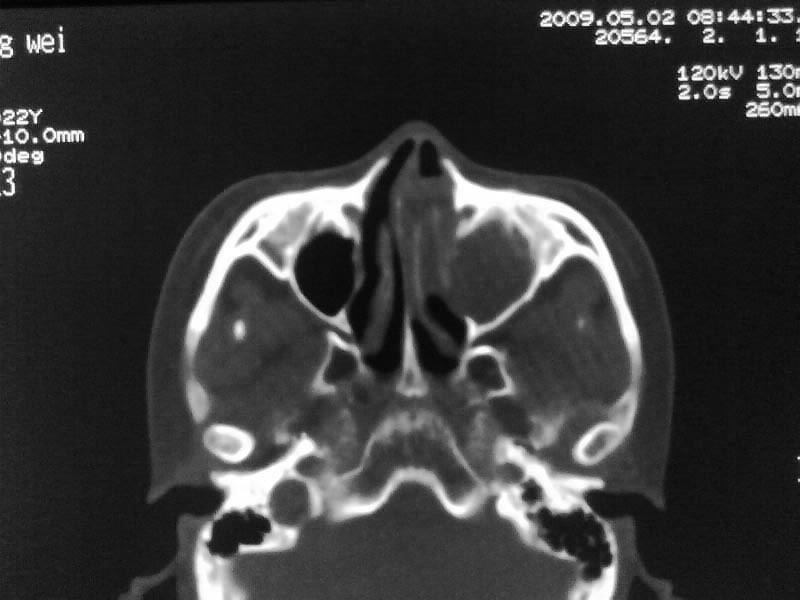

以下是引用zjzjr在2009-5-3 9:59:00的发言:[br]左侧鼻腔息肉、左侧筛窦、上颌窦炎症。双侧下鼻甲粘膜肥厚。

以下是引用随光逐影在2009-5-3 13:02:00的发言:[br]1)左侧鼻腔新生物(息肉可能)。2)左侧上颌窦及左侧筛窦炎症。3)双侧下鼻甲黏膜肥厚。